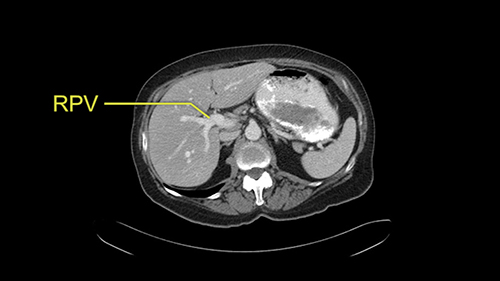

![[RHA]](jpg/preop_sg_moment3.jpg)

The only other most important feature that I usually consider is the portal vein split or the bifurcation, especially if doing a major liver resection like a right lobe. I like to look at the length of the common right portal vein trunk which looks like its probably long enough to put a stapler on. Final decision would be in the OR. If it wasn’t long enough and I was concerned about injuring the bifurcation or the left portal vein, then I would divide the Segment 5-8 and 6-7 portal tracks individually.

![[LPV]](jpg/preop_sg_moment4b.jpg)

This patient has an interesting minor anomaly with what looks like a Segment 7 portal vein coming off close to the bifurcation of the right portal vein but again if I was doing a right lobe which is my plan, this wouldn’t be an issue.